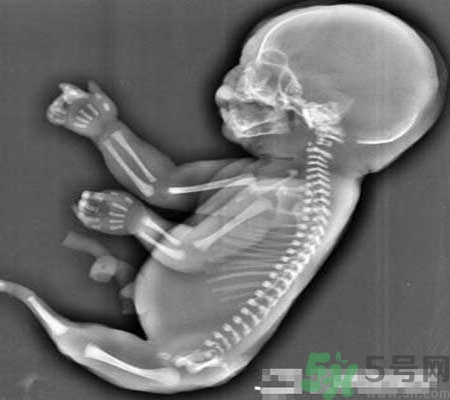

近日一個(gè)媽媽懷上人魚寶寶的檢查讓醫(yī)生大吃一驚。23歲的吳女士(化姓)前往宜昌市婦幼保健院孕檢,結(jié)果讓超聲科醫(yī)生愣住了:胎兒下肢無(wú)雙腿,只有一條類似于美人魚的“尾巴”。8月8日日,記者從宜昌市婦幼保健院獲悉,這是一種十分罕見的畸形,已終止妊娠。

當(dāng)時(shí)經(jīng)超聲檢查發(fā)現(xiàn),孕婦宮腔內(nèi)未見羊水暗區(qū),借助胎兒骨骼影像順序連續(xù)掃查,發(fā)現(xiàn)胎兒頭顱、胸腔、雙上肢,也可以看到一個(gè)跳動(dòng)的心臟。但下肢只找到一條股骨,未見雙腿、膀胱,只有一側(cè)發(fā)育不良的腎臟。